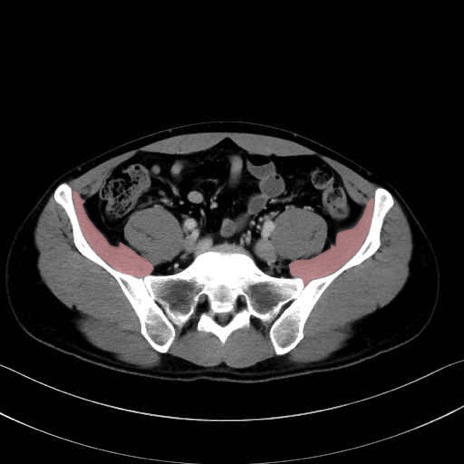

腸骨筋 (Iliacus)